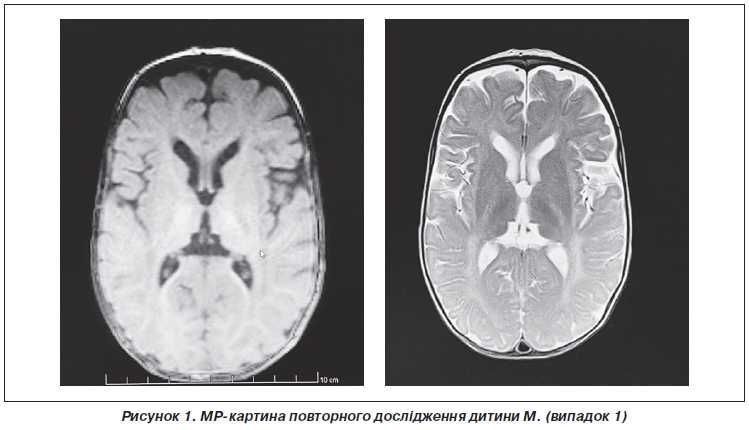

У семимісячному віці дитині було зроблено повторне МРТ-дослідження головного мозку з наступним висновком: на тлі дифузних помірно виражених атрофічних змін паренхіми півкуль головного мозку простежуються великі ділянки гіпо/демієлінізації в ділянці базальних ядер, у перивентрикулярних відділах із поширенням по білій речовині напівовальних центрів до субкортикальних відділів потиличних, тім’яних, дещо менше — скроневих і лобових, «тигроїдного» рисунка. Візуалізується виражене уповільнення дифузії у проєкції кортикоспінальних трактів обох півкуль головного мозку. Крім того, на тлі зменшення в обсязі паренхіми мозочка визначаються симетричні хмароподібні ділянки демієлінізації на рівні середніх ніжок мозочка, біля зубчастих ядер. Потовщення хіазми та проксимальних сегментів зорових нервів. Явища замісної вентрикулодилатації. МР-картина може відповідати нейродегенеративному процесу (МР-картина суспектна синдрому Crabbe та MLD) (рис. 1).

/36.jpg)